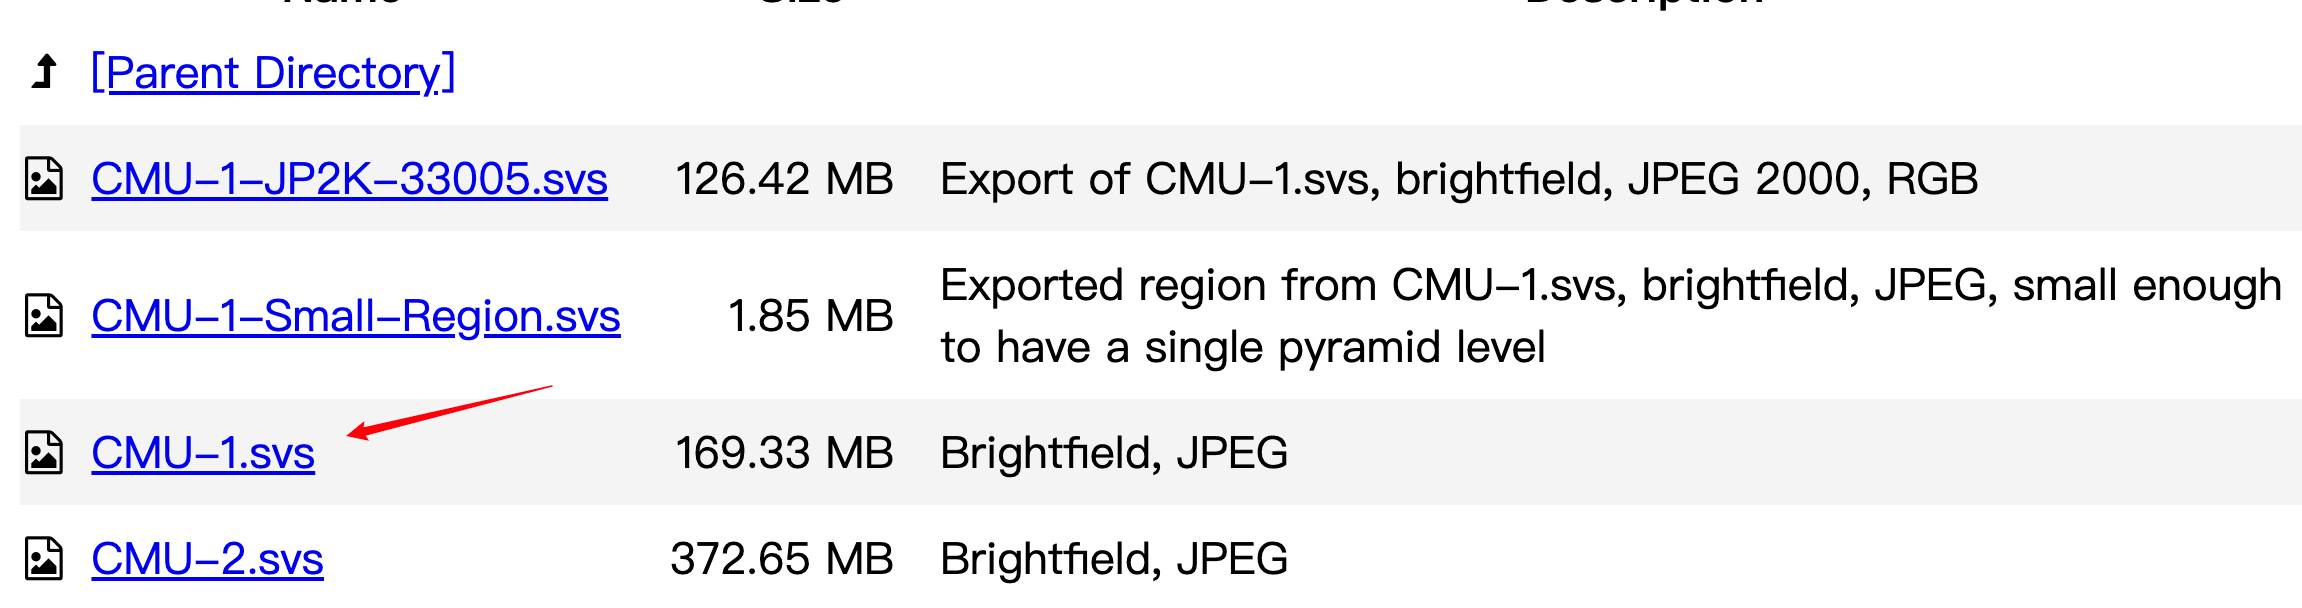

- CMU-1.svs:大小为169.33 MB,是一个明场JPEG格式的图像,也是CC0许可。

我们现在下载第三个图像。